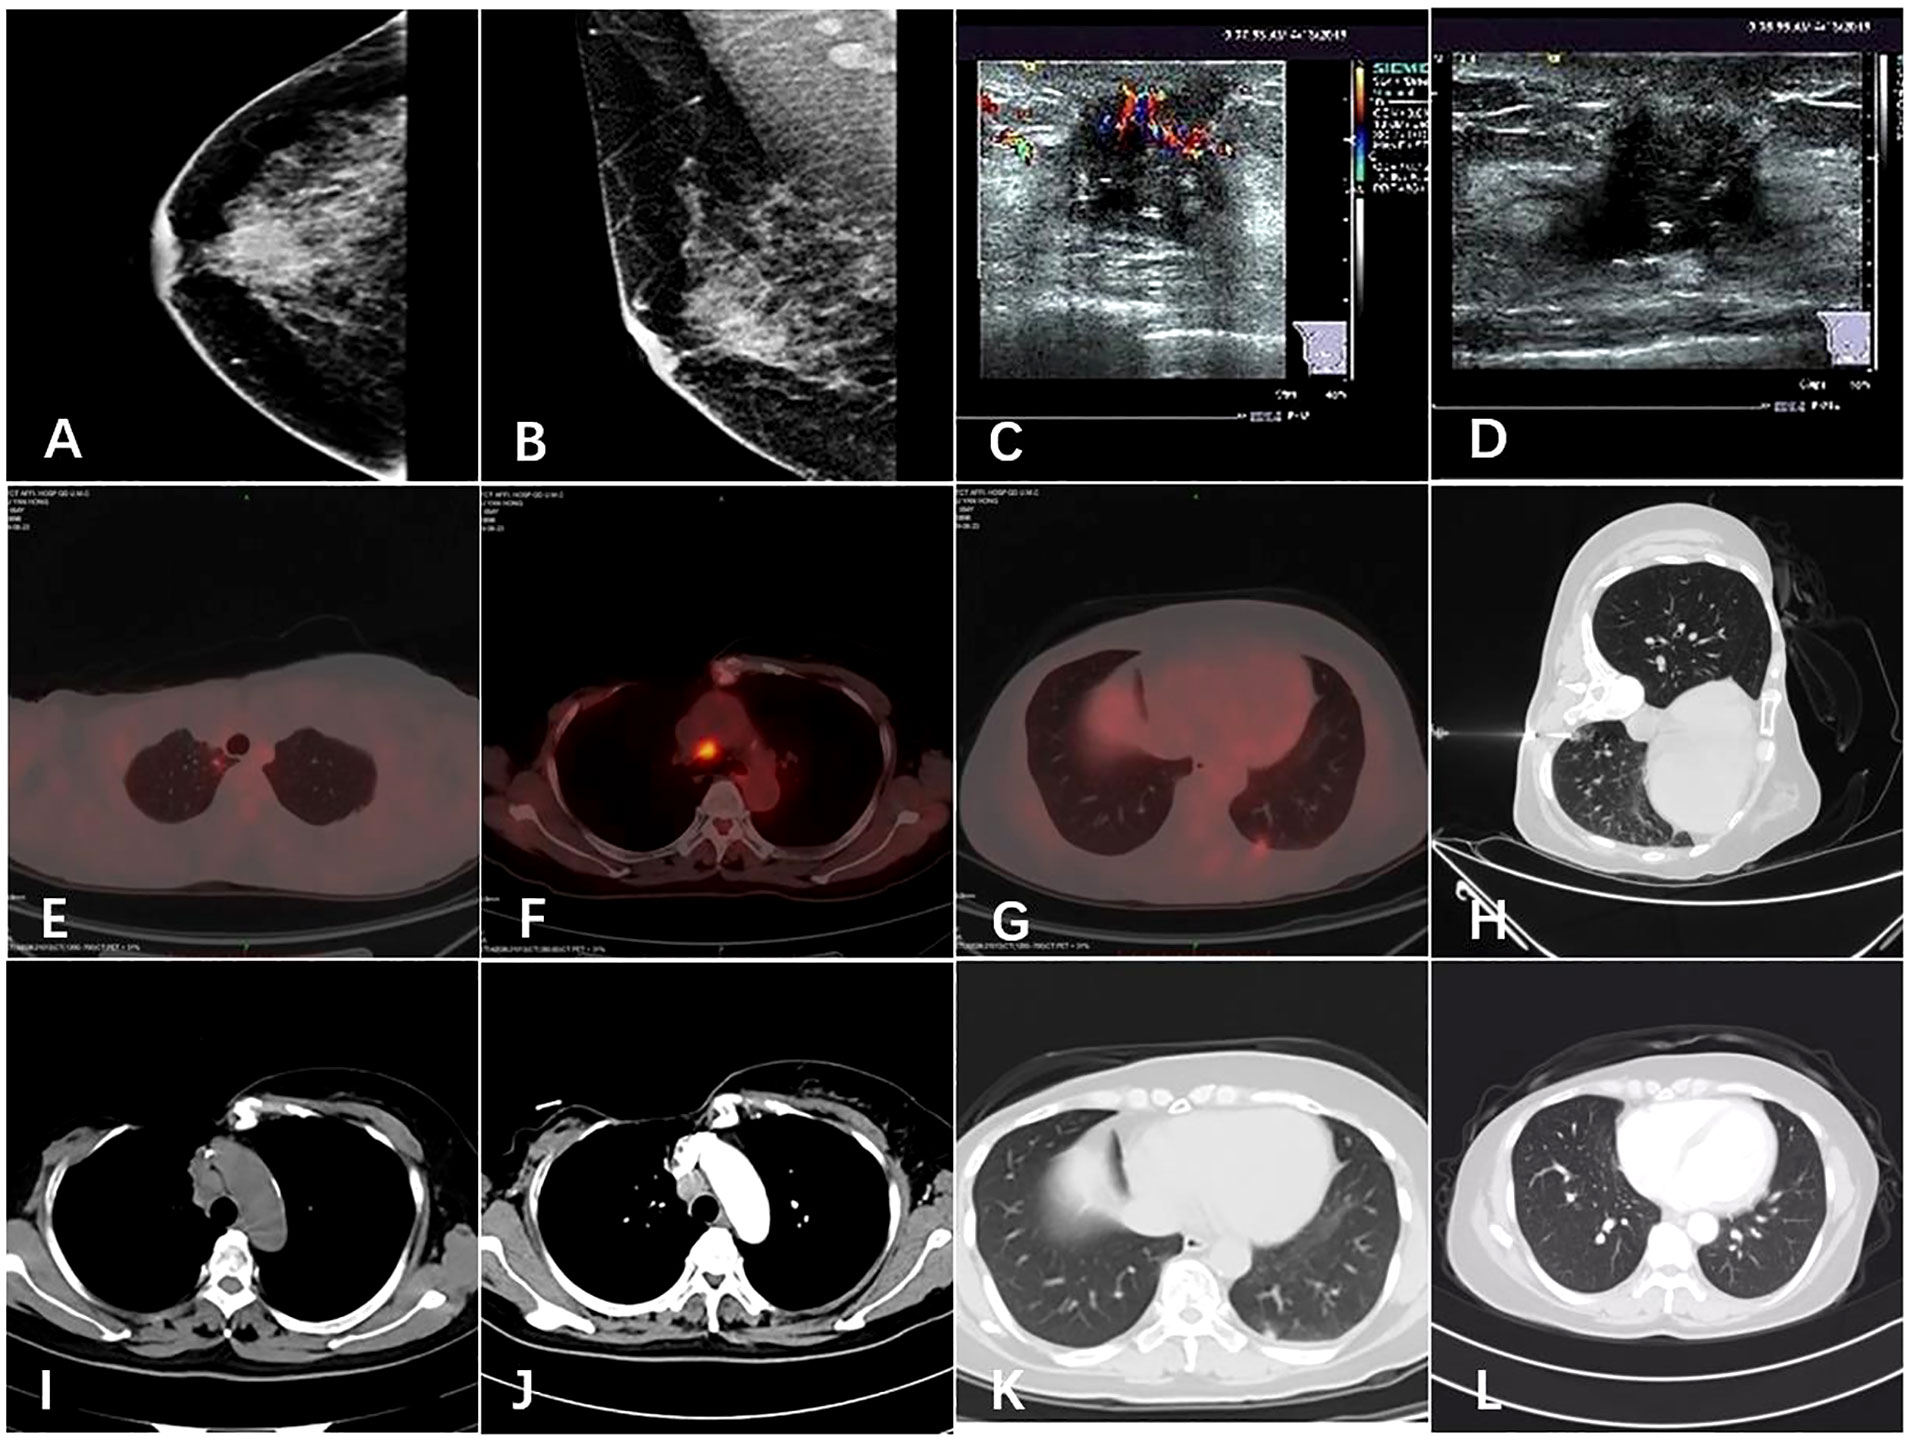

Breast Cancer Treatment (PDQ®) - American Association for。nejmcpc2309499_f1.jpg。Frontiers | (KAUH-BCMD) dataset: advancing mammographic。乳がんに関する最新の情報を提供するモノグラフ。Breast cancer: Know the facts | CNN。病理学や治療法についての詳細な章を含む。。- タイトル: Breast Cancer- 編集者: B. Hoogstraten, I. Burn, H.J. G. Bloom- 出版社: Springer-Verlag- 内容: 乳がんに関する最新の情報を提供するモノグラフ- 特徴: 病理学、診断、治療法についての詳細な章を含む- シリーズ名: UICCご覧いただきありがとうございます。視能検査学。